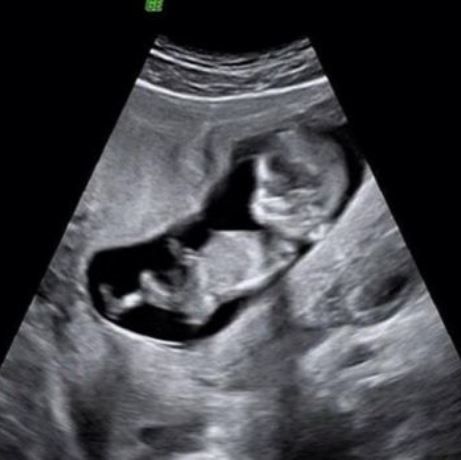

Πασίγνωστη Ελληνίδα ηθοποιός περιμένει το δεύτερο παιδί της & δείχνει το υπερηχογράφημα

Πολλές είναι οι γυναίκες της σόου μπιζ, τελευταία, που μοιράζονται την πιο όμορφη στιγμή της ζωής τους, στα social media με τους διαδικτυακούς τους φίλους...